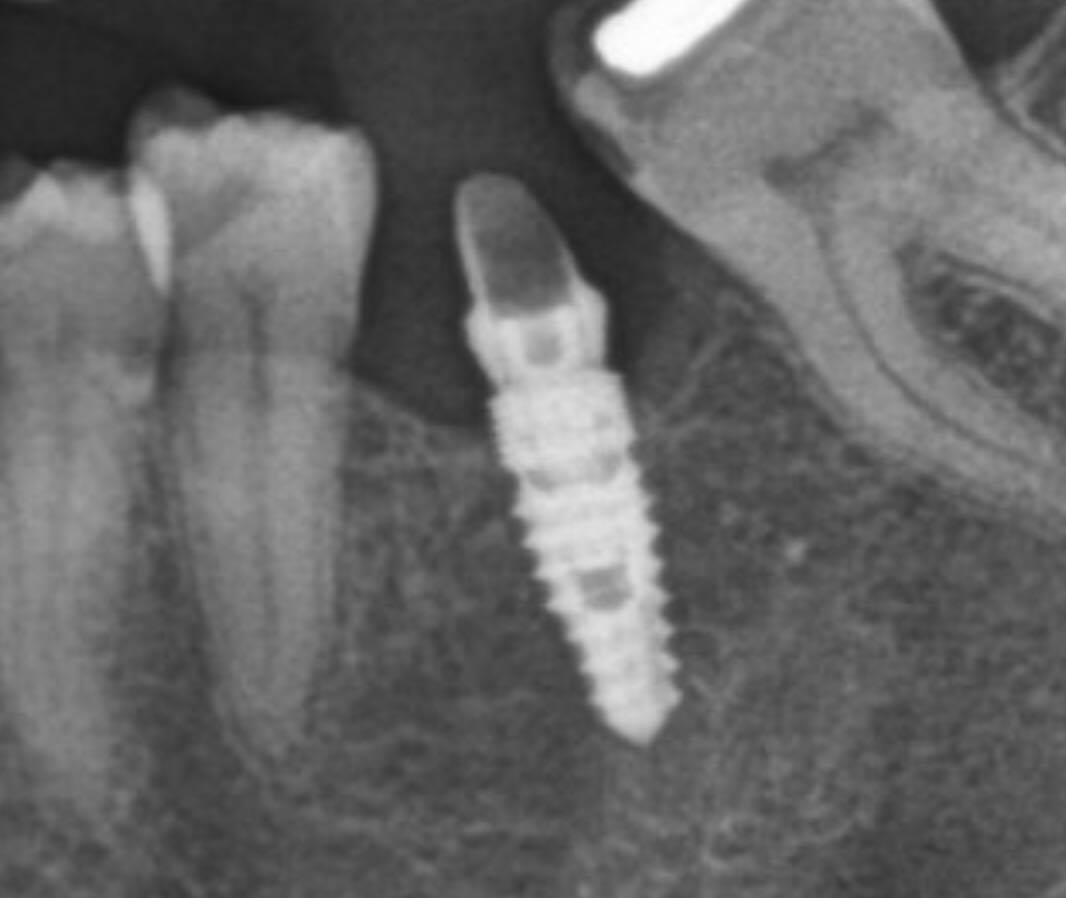

Je commence ci joint la pano

je sais juste que l'implant date d'environ 5 ans; la personne ne se rappelle pas qui lui a fait.

l'implant est conique, le col a des micros filets, l'apex est pointu, et la connexion est interne.

je pense pas que ça soit un dentaurum

le tiologic à une spire dédoublée et le tiolox n'a pas de microspire au col.

sur la radio la spire est simple et le col est microspiré

m'est d'avis que tu aurais une RETRO et non un crop de la pano tu verrais plus de détails....

et donc on aurais une meilleure base de recherche....

je me demande si c'est pas un paltop

j'ai pas de retro

son prat m'a envoyé une retro, mais c'est pas mieux que la pano